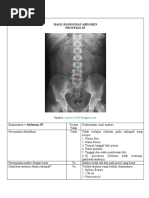

A. Proyeksi Wangesteen Rice

1) Posisi AP

Untuk melihat ada tidaknya atresia ani dan untuk melihat beratnya distensi

2)  Posisi Lateral

Untuk melihat ketinggian atresia ani.

B. Lateral Prone Cross Table

Alternatif pemeriksaan invertogram pada kasus atresia ani untuk memperlihatkan

bayangan udara di dalam colon mencapai batas maksimal tinggi/ naik di daerah

rectum bagian distal.